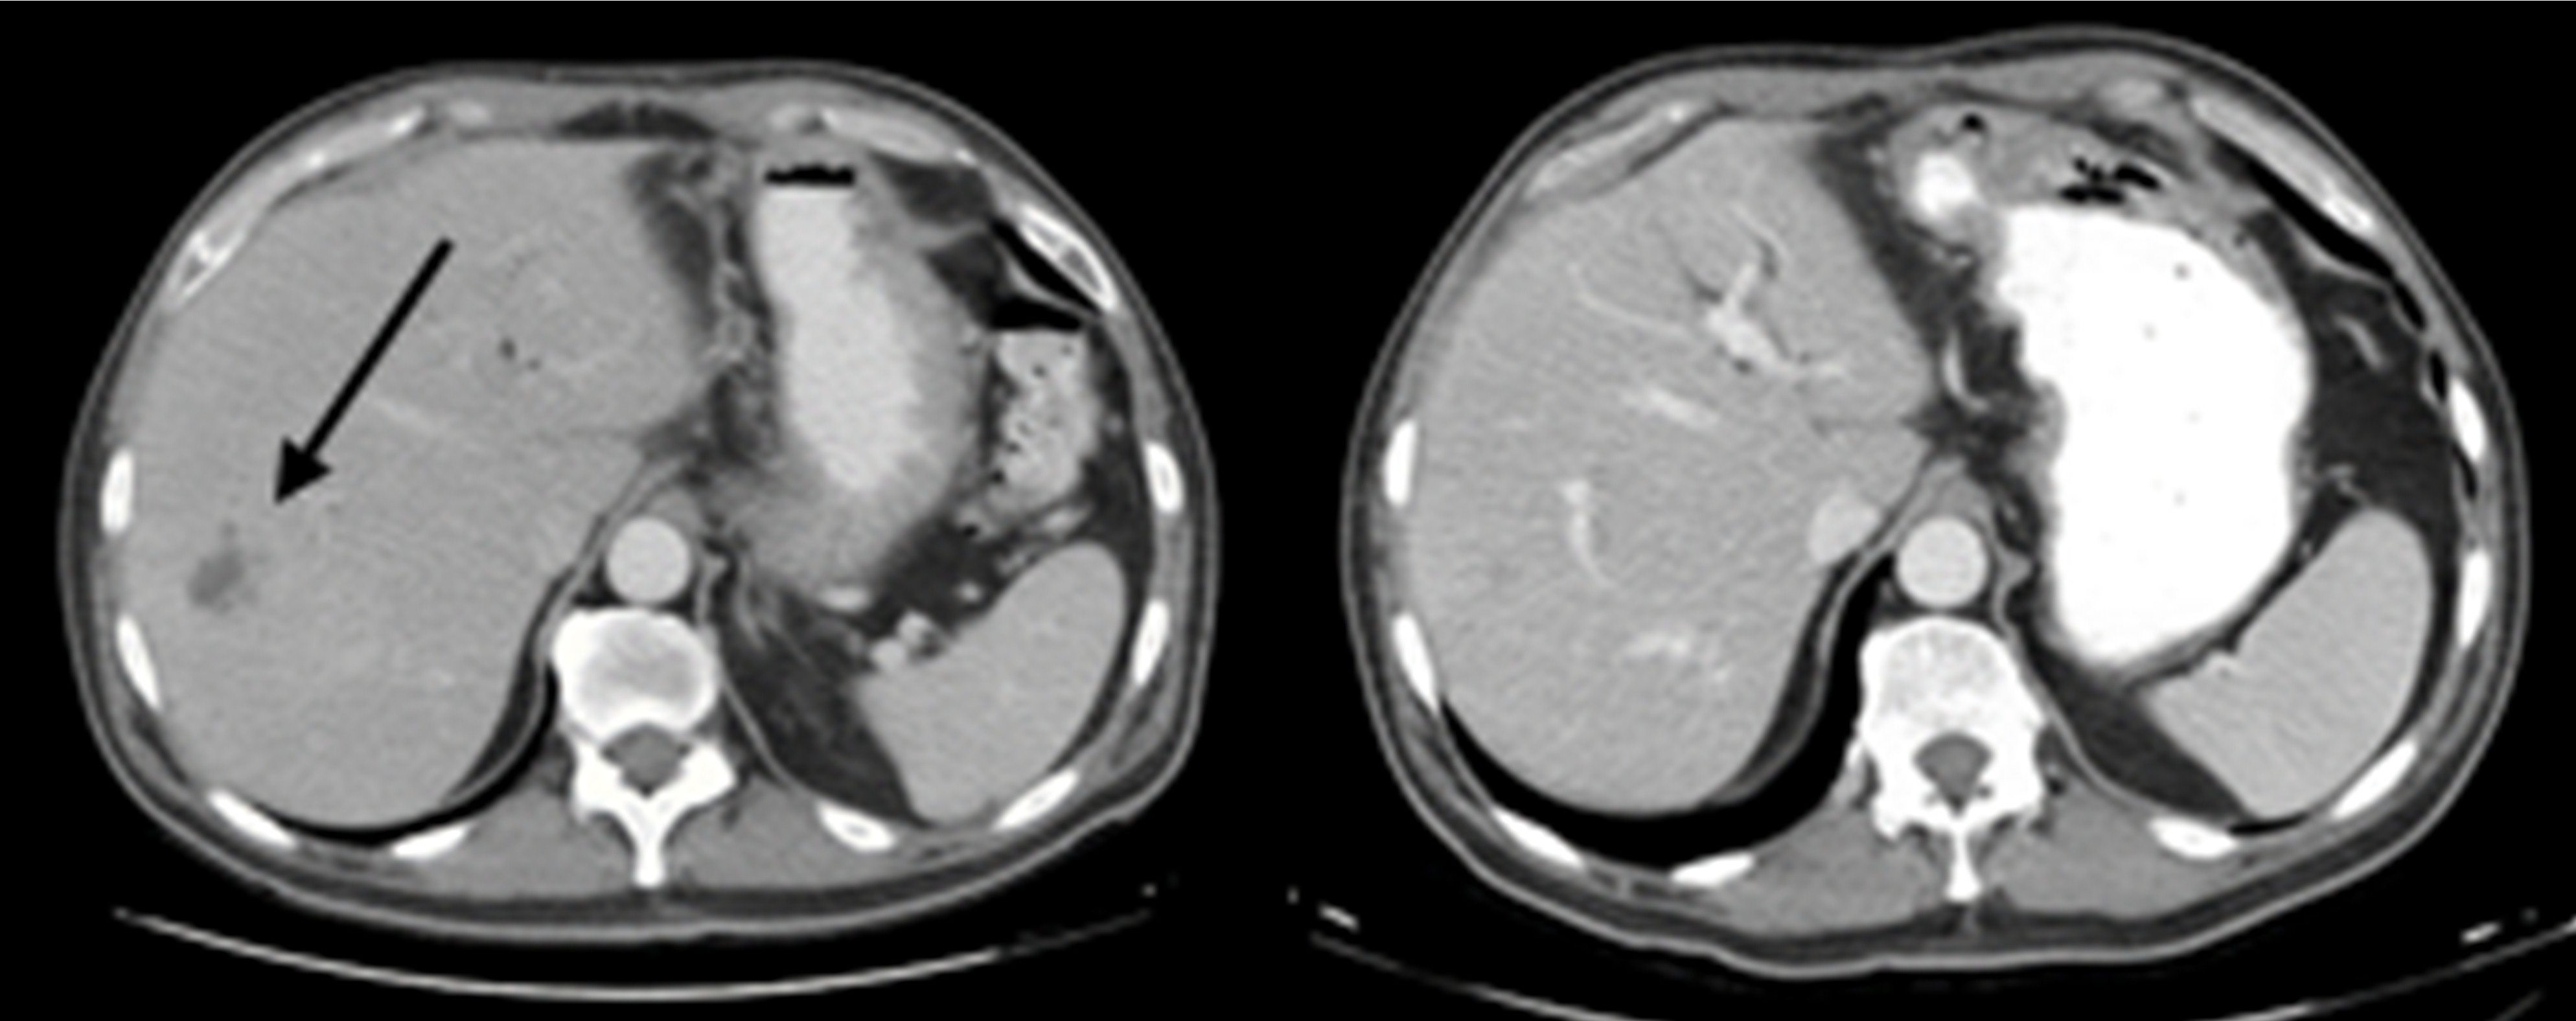

膵臓癌 多発肝臓転移症例 4年4ヵ月間生存 症例

治療症例の紹介 膵臓癌 すいぞうがん 大阪本町csクリニック

転移性膵臓癌 長期生存例 英文と和訳 写 を読む 獨樂獨歩